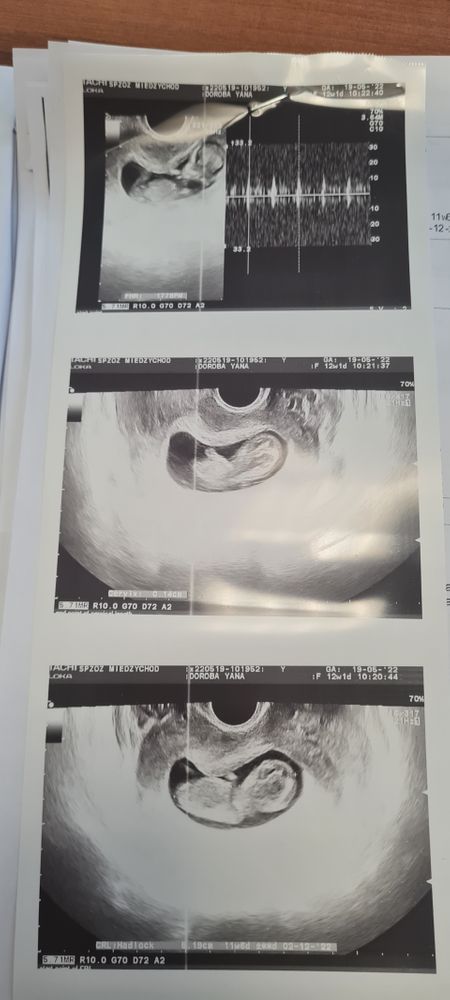

Яна, тоже заметила , что начала часто чихать 🤔 а дрыгается он там и правда смешно 😄 плавает как на горке , на скрининге смотрели сначала без мужа , спал, муж зашёл , такие выкрутасы начал показывать 😄😄😄